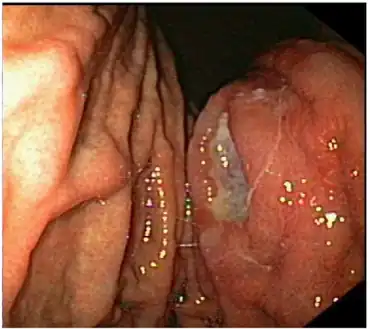

| Endoscopic image of gastric MALT lymphoma taken in body of stomach in patient who presented with upper GI hemorrhage. Appearance is similar to gastric ulcer with adherent blood clot. | |

These lymphomas are difficult to differentiate from gastric adenocarcinoma. The lesions are usually ulcers with a ragged, thickened mucosal pattern on contrast radiographs.

The diagnosis is typically made by biopsy at the time of endoscopy. Several endoscopic findings have been reported, including solitary ulcers, thickened gastric folds, mass lesions and nodules. As there may be infiltration of the submucosa, larger biopsy forceps, endoscopic ultrasound guided biopsy, endoscopic submucosal resection, or laparotomy may be required to obtain tissue.